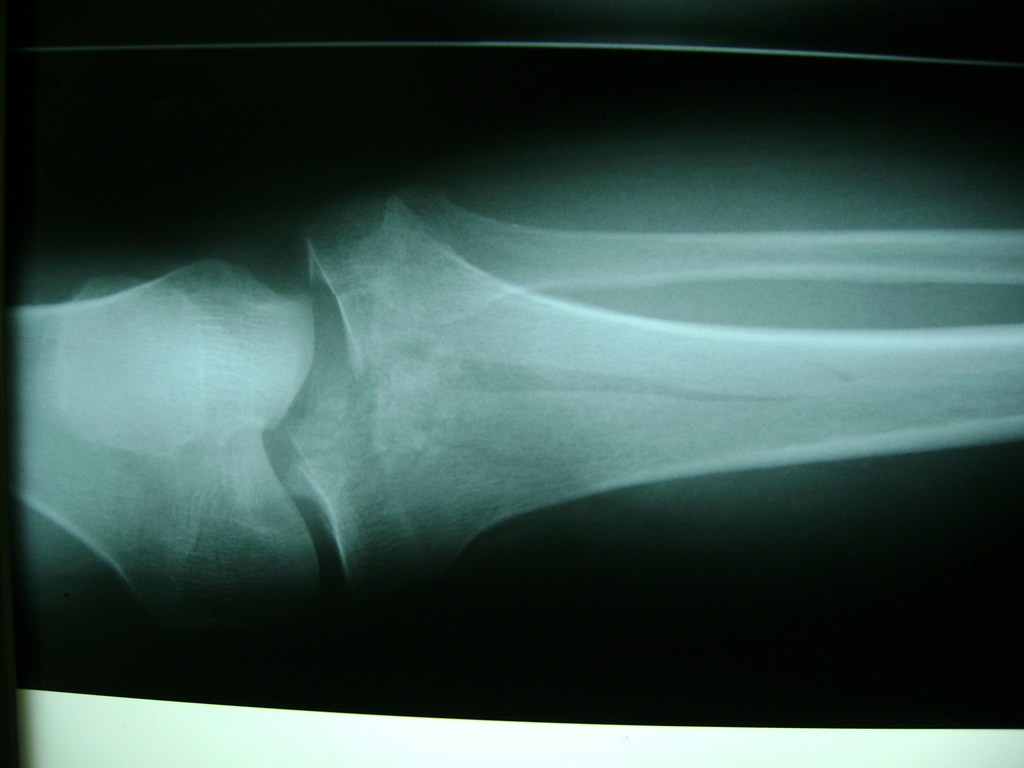

Húmero - Rodilla

La artroscopia de rodilla es un cirugía en el cual la estructura interna de la articulación es examinada ya sea para realizar un diagnostico o para realizar un tratamiento, este procedimiento se realiza utilizando un instrumento parecido a un pequeño tubo llamado artroscopio.